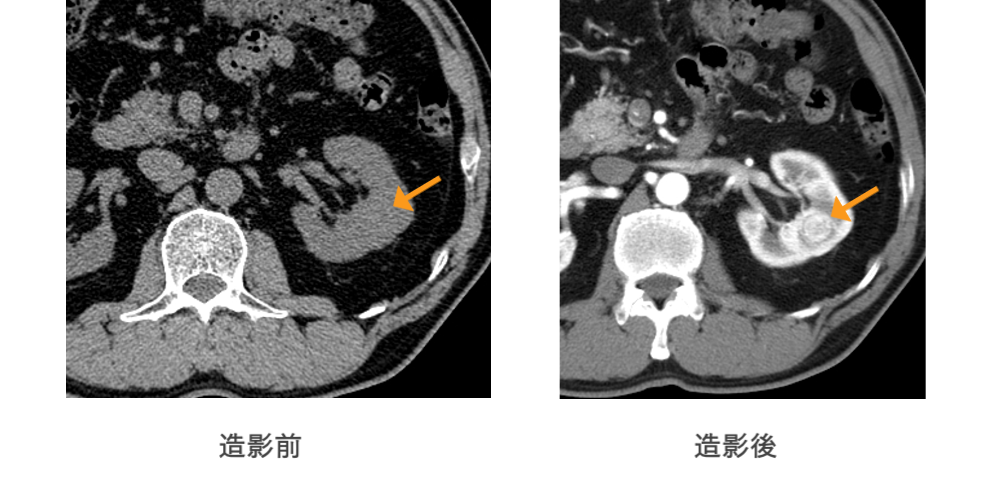

当院では検査目的に応じ、ヨード造影剤を使用した造影CT検査を行います。

造影剤を血管内に投与することで、コントラストのついた画像を得ることができ、非造影CTでは診断不可能な病変を検出することができます。

非造影では認識できない病変が造影後は明瞭に認識されます。

(腎癌の症例)